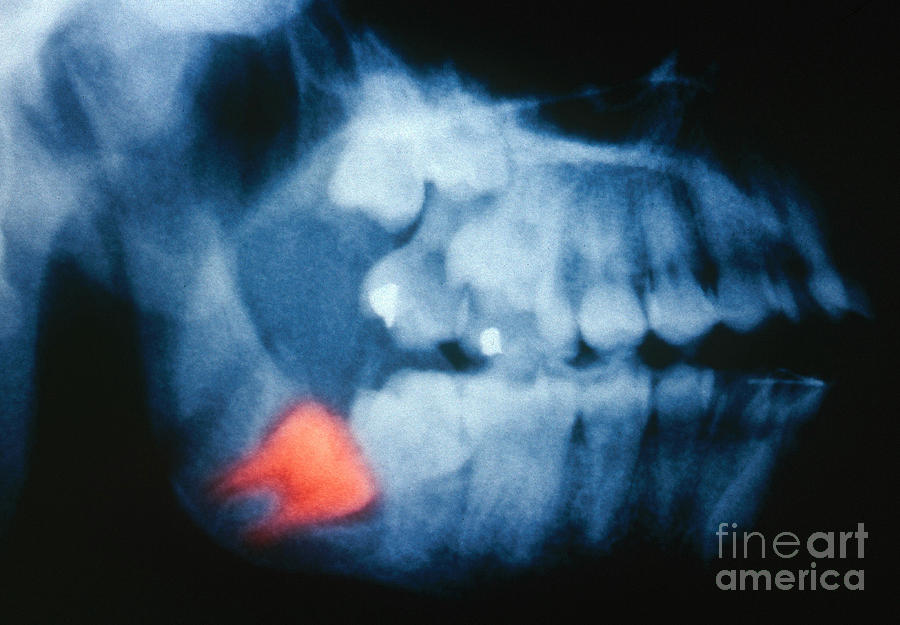

www.shutterstock.comWISDOM TOOTH, X RAY Stock Photo - Alamy

www.shutterstock.comWISDOM TOOTH, X RAY Stock Photo - Alamy

www.alamy.comWISDOM TOOTH, X RAY Stock Photo - Alamy

www.alamy.comWISDOM TOOTH, X RAY Stock Photo - Alamy